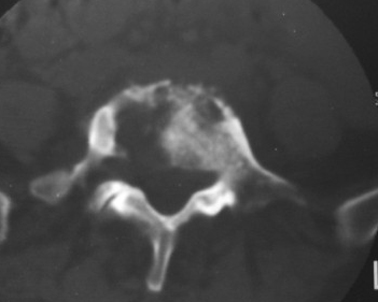

以下是引用dyqct在2007-3-1 18:04:00的发言:[br]腰5、骶1呈溶冰状骨质破坏,边界清楚,无明显硬化,内见多数沙粒状死骨,周围软组织肿胀。[br]考虑:腰5、骶1结核,建议严格抗结核治疗后复查。

以下是引用gaoxiao在2007-3-1 18:02:00的发言:[br]腰5骶1椎体见骨质破坏,其内见死骨形成,椎前软组织肿胀,感染性病变,腰骶椎tb。

以下是引用gaozhengyi在2007-3-1 19:39:00的发言:[br]骨质破坏并砂砾样死骨为椎体结核的表现。椎体结核骨质破坏区的特点是呈虫蚀状,常可见硬化缘。死骨表现为片状高密度影,正如本例。